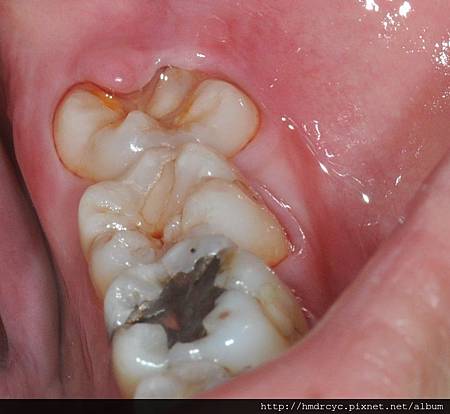

當智齒長歪頂到前面的牙齒

細菌跑進來的時候會無法清潔

頂到前面牙齒的地方會蛀牙

而牙肉包住的地方會牙肉發炎牙周病

往往不是只露出一點點

就是沒有完全露出